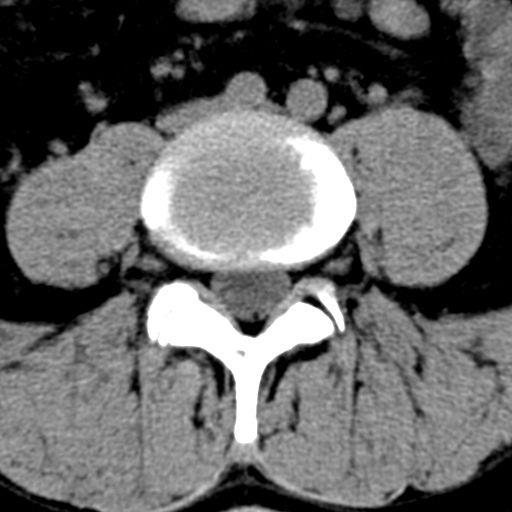

Auch hier reicht zumeist Röntgenaufnahme in Funktion sowie eine Kernspintomographie oder eine Computertomographie aus. Bei einem Wirbelgleiten oder einer Verengung auf mehreren Höhen ist eine Myelographie nach wie vor die Untersuchung, die die wertvollsten Ergebnisse im Hinblick auf eine genaue Operationsplanung liefert.